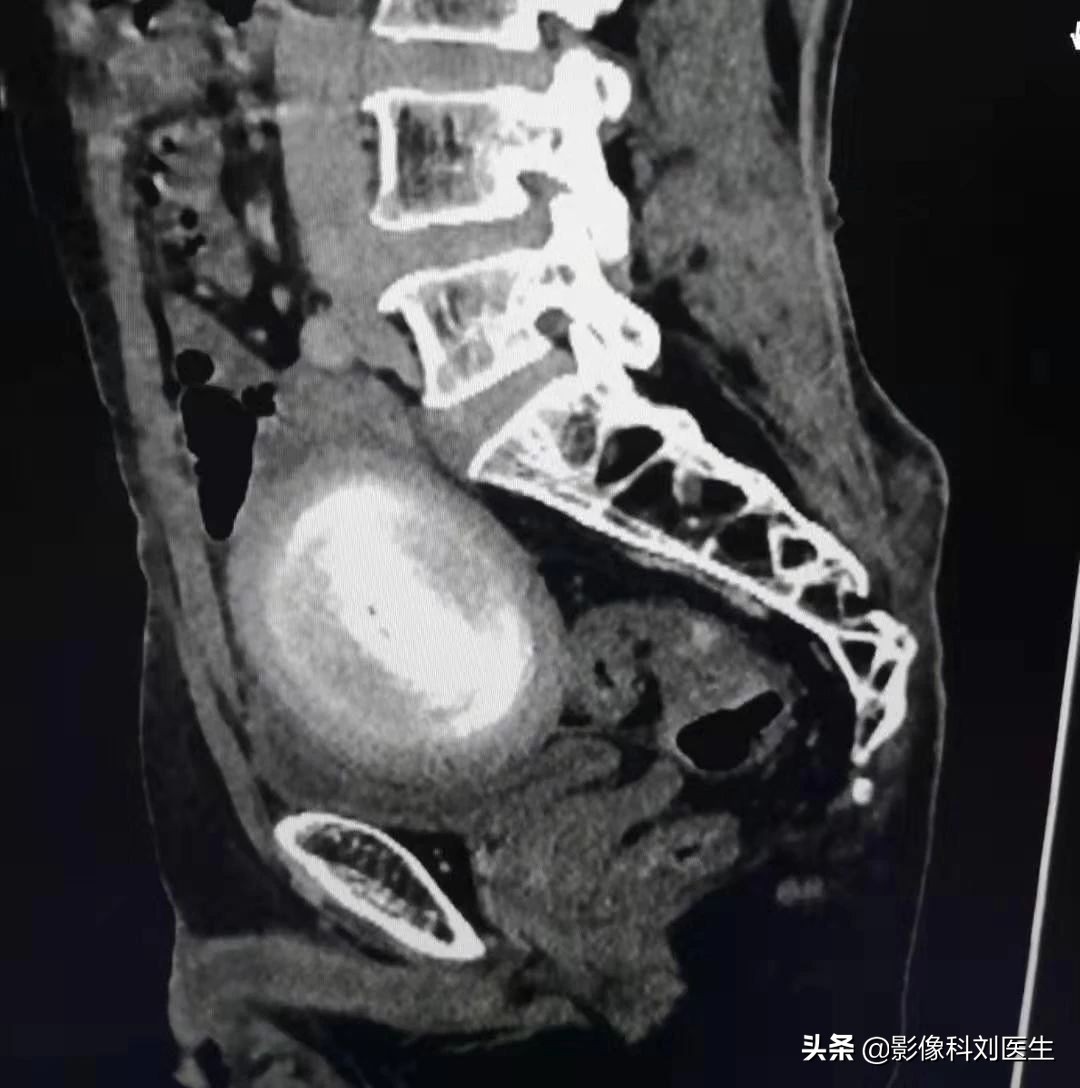

今年88岁的李大爷,虽然年龄比较大了,但身体一向比较好,平时也经常锻炼、很少住院,而就在最近,李大爷逐渐的出现了腹部疼痛,刚开始的时候,疼痛比较轻,呈隐痛,大爷以为是自己吃了什么不卫生的东西,也就没太在意,认为忍一忍就过去了。但是一周过去了,疼痛不但没有减轻,反而越发的严重了,李大爷感觉到了不对劲,赶紧来到了医院进行检查。来到医院后,接诊的外科医生发现大爷精神较差,下腹部压痛明显、腹胀,于是立即开了CT检查来我科检查,而CT检查一做,我们意外发现,李大爷的盆腔内见大小约9.5x6.5cm的高密度肿块,边缘光滑,犹如“鸭蛋”大小。与周围结构分界尚清除。由于平时我们也很少遇到类似病例,所以一时也无法定性诊断,不过观察比邻关系,应该可以进行手术治疗,于是便马上连续了外科医生,希望能得到他术后的病理诊断,从而进行学习补充。

CT矢状位